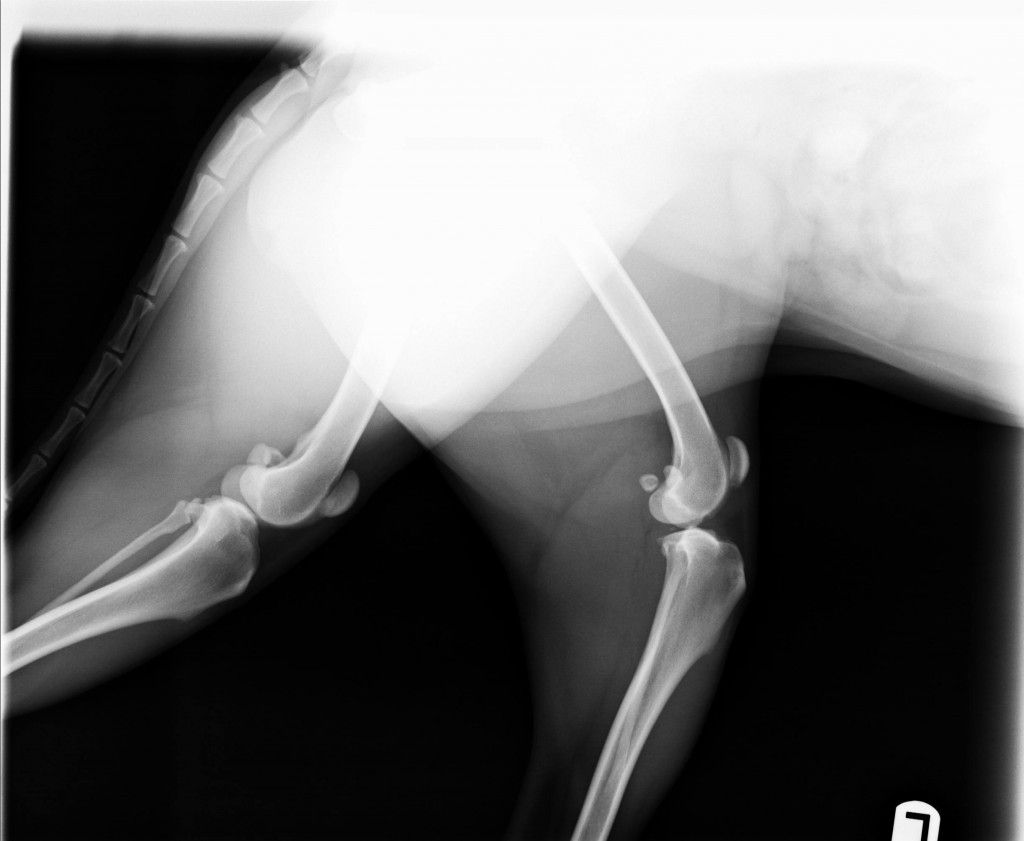

Audrey’s X-rays

Here are the X-Rays from Audrey’s knee surgery